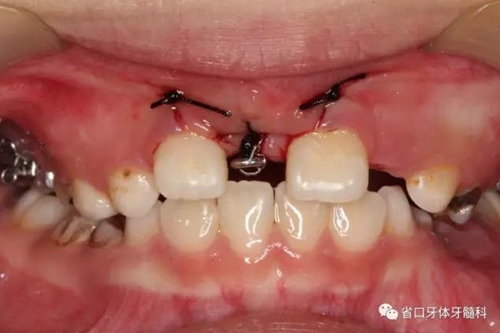

11開(kāi)窗,粘接附件進(jìn)行牽引

腭托式牽引裝置